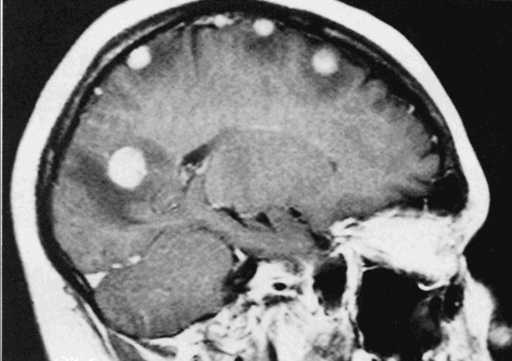

На заключительном этапе злокачественные клетки поражают ткань печени и почек, кости, проникают в головной мозг. Это вызывает тяжёлые боли, с которыми не справляются анальгетики. Абсолютное выздоровление (без рецидивов) в течение описываемого этапа происходит очень редко. Срок жизни онкобольных со злокачественными образованиями, распространившимися на сердце или печень, не больше 2-х месяцев. С диагнозом саркома 4 стадии прогноз не превышает 8-10% длительности жизни людей в течение 4-6 лет.

При мелкоклеточном раке легкого 4 стадии прогноз менее благоприятный, но и для таких пациентов существуют эффективные методы лечения. Если состояние больного позволяет, назначают химиопрепараты: этопозид в сочетании с цисплатином или карбоплатином. В некоторых случаях это помогает добиться того, опухолевые очаги перестают выявляться с помощью неинвазивных методов диагностики. Но, как правило, даже в таких ситуациях через некоторое время рак возвращается.Если пациент успешно перенес курс химиотерапии, назначают лучевую терапию грудной клетки. Затем врач назначает профилактическое облучение головного мозга, так как при мелкоклеточном раке очень высок риск метастазирования.